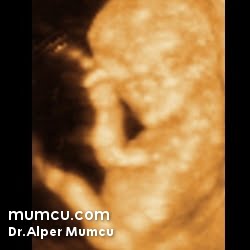

3 Boyutlu ultrason resimleri

Bu sayfadaki fotoğraflar degişik zamanlarda ve farklı hastalarda Dr. Alper Mumcu tarafından çekilmiştir.

13 haftalık gebelik